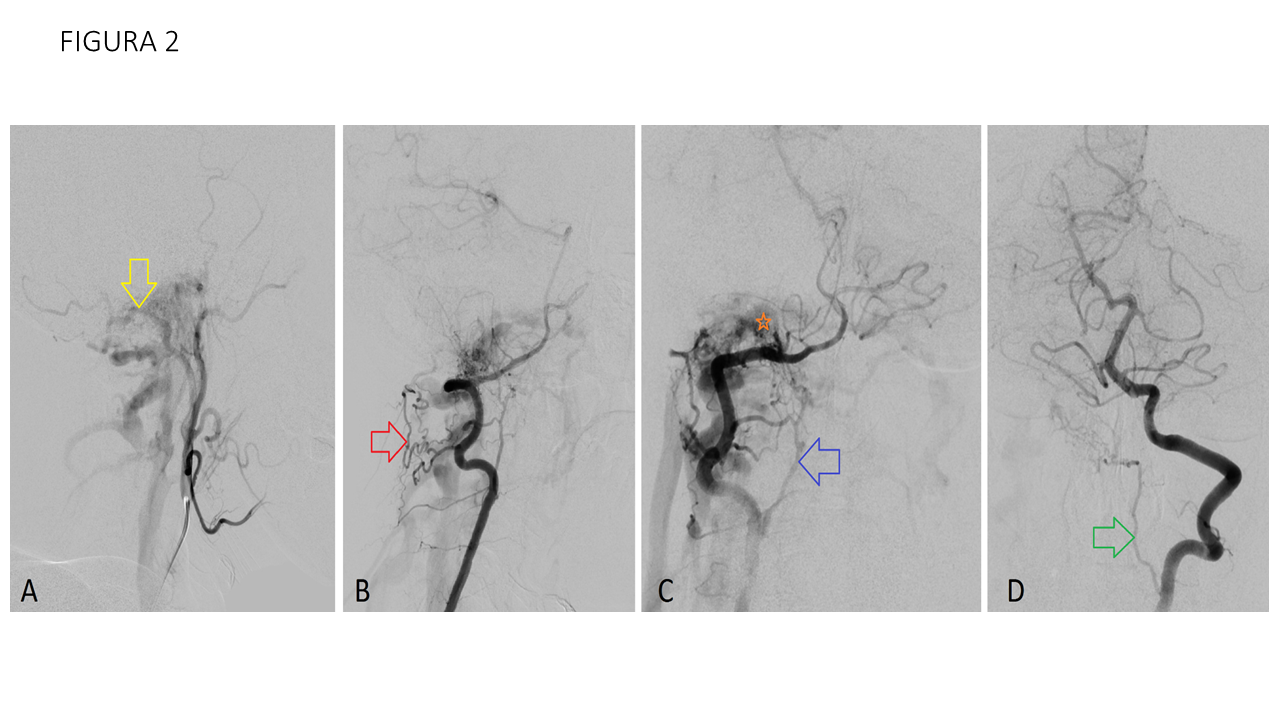

FIGURA 2 Se realiza arteriografía de ambas arterias carótidas internas y externas y vertebrales. En proyección lateral de arteria carótida externa derecha (A) se objetiva hipertrofia de arteria occipital (flecha amarilla) y opacificación en fase temprana de la vena yugular derecha. En las proyecciones lateral (B) y anteroposterior (C) de arteria vertebral derecha, se objetiva hipertrofia de las rama durales de arcada odontoidea (flecha azul) y de las anastomosis de la arteria cervical profunda (flecha roja), conectando ambas a la altura del canal hipogloso derecho probablemente con la vena condílea, objetivandose relleno precoz de ésta y del bulbo yugular (asterisco naranja). En la inyección desde la arteria vertebral izquierda (D) se objetiva hipertrofia de rama dural que da a la arcada odontoidea (flecha verde). Los hallazgos angiográficos están en relación con fístula arteriovenosa dural condílea derecha correspondiente con clasificación IIa de Cognard. Se descartaron aportes desde ambas carótidas internas.